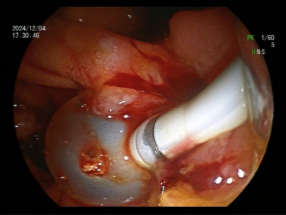

十二指肠乳头藏匿“隐秘角落” ,多发憩室让取石之路“荆棘丛生”,意味着这是一台高难度ERCP,面对这一复杂情况,黄华丽主任凭借其10余年丰富的ERCP实战经验,决定迎难而上,为患者实施ERCP取石术。术前黄华丽主任带领团队对患者的病情进行了复盘分析,鉴于传统手术取石风险较高,内镜微创手术伤害小,因此决定冒险采用ERCP取石术。充分沟通手术的必要性及十二指肠降部解剖结构异常导致手术难度,制定了详细的手术方案,并对手术过程中可能出现的各种情况进行了充分的预判和应对准备。患者及家属果断同意行ERCP术。术中,黄华丽主任通过巧妙调整内镜角度、最终找到藏匿在憩室旁边被挤压的十二指肠乳头,因结构异常只能长镜身插管,成功插管进行造影以明确结石的位置、大小和数量,取石球囊反复取石,成功将患者胆总管内的结石一一取出(见图2、3、4、5)。整个取石过程顺利,未出现明显并发症。患者术后恢复情况良好,未出现明显的疼痛和不适。患者术后腹痛、发热症状完全消失,黄疸逐渐消退。

图4 球囊取石过程